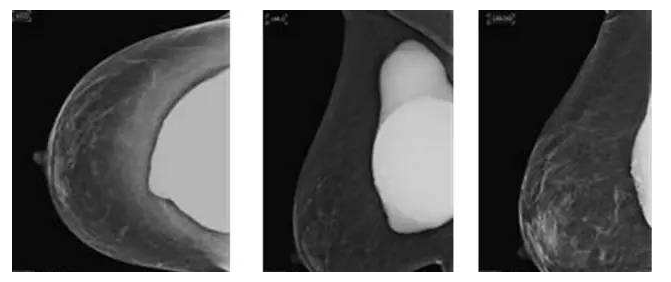

假体隆胸手术发展至今已有几十年历程,随之时代的发展,医学的进步,现代隆胸技术在不断升级,假体质量也在不断提高。现代信息的广泛传播,也让受众对于隆胸手术的了解全面化。一台成功的隆胸手术可以维持10年的时间,那么为什么是10年成为了隆胸的关键时期?10年后隆胸的人会面临怎样的问题?

因为假体质量不同、医生操作方式不同、个人体质存在差异,所以具体的存放时间无法被预估。所以假体隆胸10年后,应每年进行B超、核磁共振检查,以确保假体的完整性和安全性,排除并发症,如遇问题,可尽早进行处理。

假体老化最常出现的现象,比如囊壁钙化,渗漏,甚至破裂,还会随着人体组织的老化出现下垂问题。

囊壁钙化:硅胶假体在胸部存放时间过长,在硅胶和自身组织包膜之间,就有可能形成钙化沉淀。轻微的钙化不会对人体造成伤害,无需在意。但如果钙化出现较大的结块,而且集中出现在假体周围,便需要做组织取出或手术。

假体渗漏、破裂:囊膜皱褶经反复运动而老化破裂,后期渗漏或破裂,有纤维囊挛缩或急性炎症现象。假体破裂的发生率虽然很低,当假体出现明显的手感变化,形态的变化,那么这个时候就可能出现了假体的破裂,如果出现假体破裂就需要置换假体。

假体松弛下垂

如果出现假体隆胸变软下垂的问题可能是假体置入层次的问题,假体如果是放在胸部腺体下,它会随着自体的胸部往下垂而一起下垂,如果假体放在胸大肌下,那么就会出现腺体往下走,而假体不往下走,就有可能形成四个胸部的情况。

最后提醒大家,一般情况下假体维持10-20年基本没有问题,不必对此过于忧虑。时常观察胸部大小变化,手感软硬程度,每年做好定期检查即可。